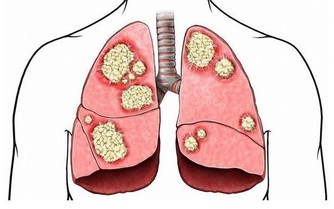

10.免疫調節機能:木瓜籽的水溶性成分,能和特定醣組成植物凝集素成份,這類成份像是蛋白質或醣蛋白,特點是能讓血球凝集。

許多研究指出,食物中的凝集素成份能刺激免疫細胞增生、調解免疫細胞、抑制腫瘤細胞生長等,木瓜籽中的凝集素有相當高的結合能力,可誘導與調節特定免疫細胞,具有免疫調節的潛力。